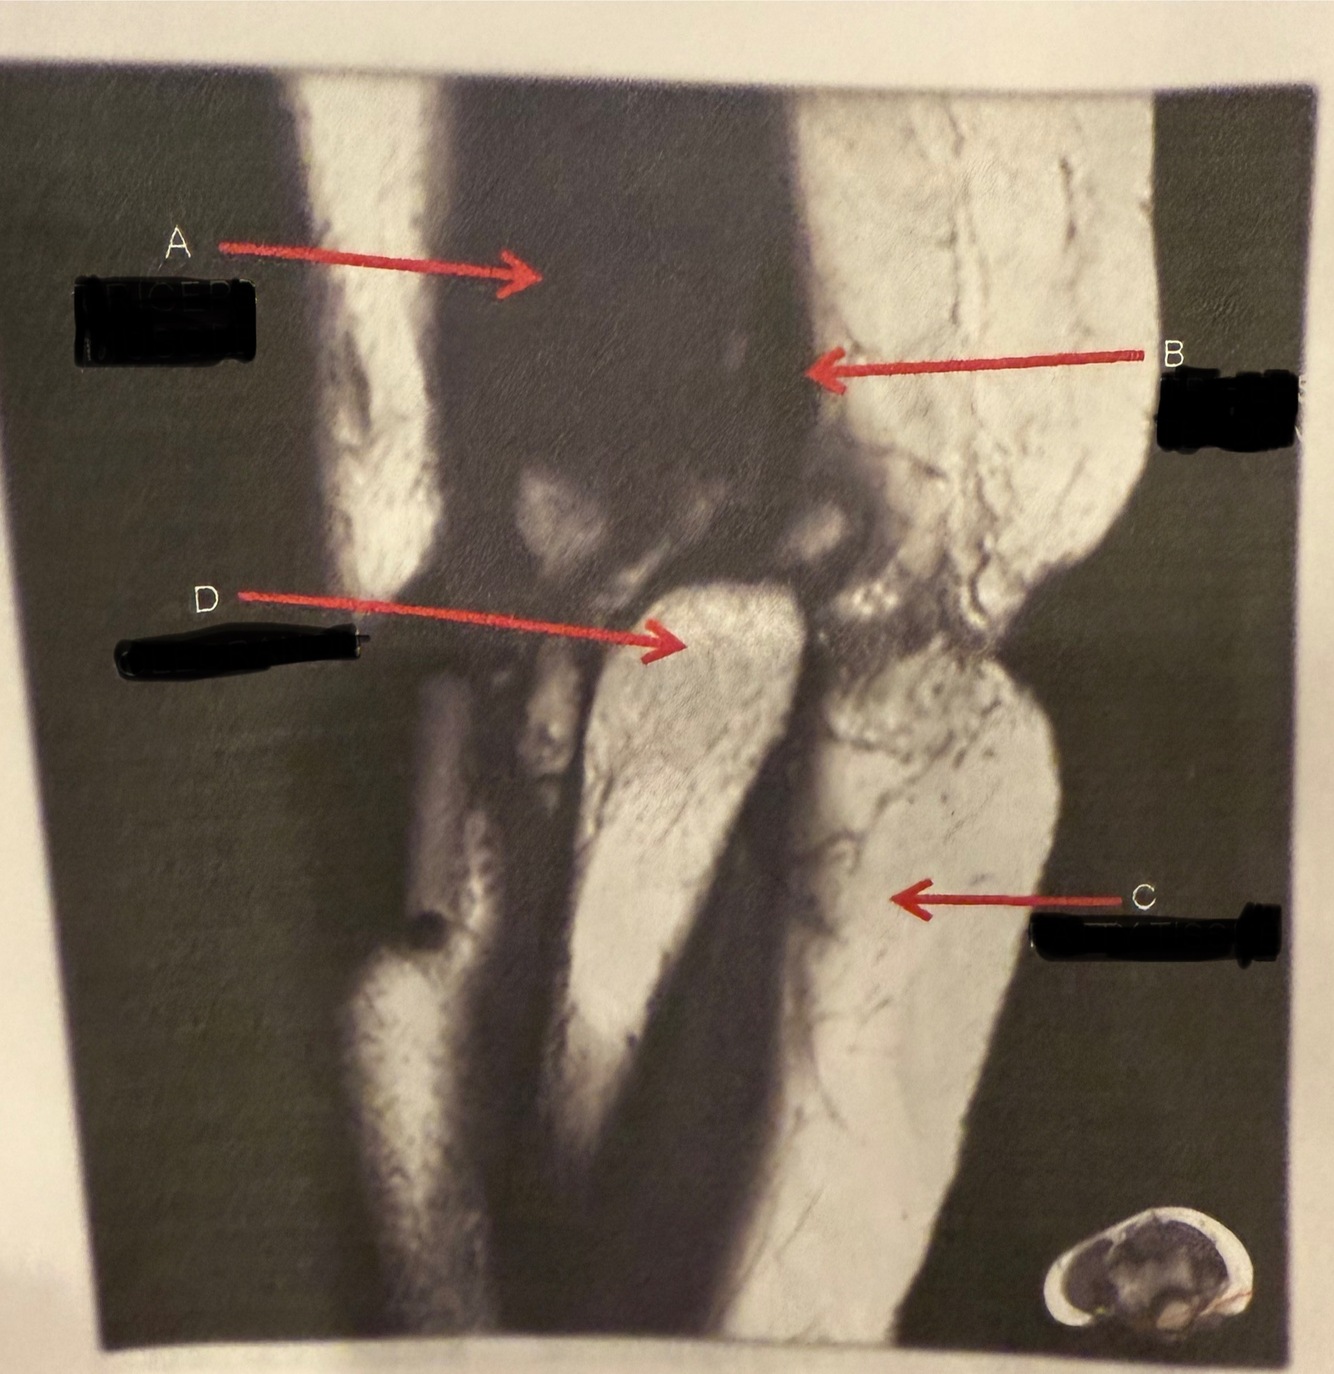

IDENTIFY A , C

A

A.TRICEPSMUSCLE

C.FATTYTISSUE